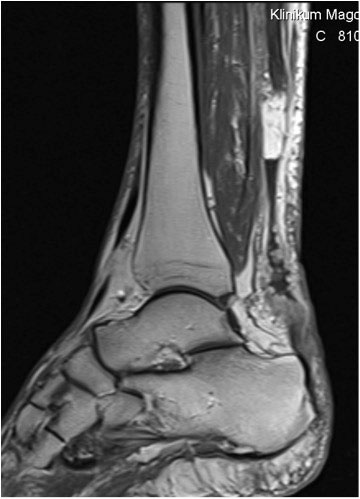

Knöcherne Ausrisse lassen sich in der seitlichen Röntgenaufnahme des Sprunggelenkes ausschließen oder beweisen (Abb. 5). Eine Sonderform bilden hier die Entenschnabelfrakturen des Kalkaneus.

Abbildung 5

Der geübte Untersucher kann anhand des seitlichen Röntgenbildes die Diagnose einer Achillessehnenruptur stellen. Die Konturen des Kager-Dreiecks – gebildet von der ventralen Begrenzung der Achillessehne, der posterioren Tibiakante und der kranialen Kalkaneuskortikalis – verstreichen im Rupturfall (Kager 1939). Die MRT- Diagnostik spielt für die Primärdiagnostik der frischen Achillessehnenruptur eine untergeordnete Rolle und ist im Normalfall nicht notwendig. Anders verhält es sich bei den chronischen Rupturen. Hier ist die MRT ein wichtiges Diagnostikum insbesondere in Hinblick auf die Beurteilung der Sehnen- und Muskeldegeneration (Abb. 6).